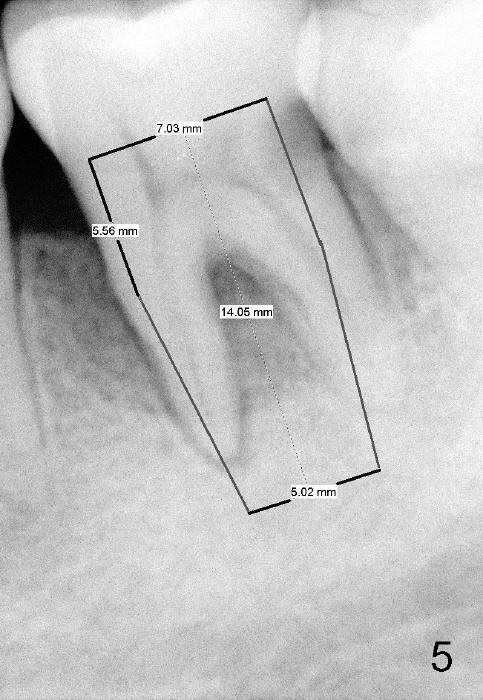

Considering severe bone resorption, a 6.9x10 mm bone-level (Fig.4) or 7x14 mm gingiva-level (Fig.5) implant does not seem to be long enough to achieve primary stability. Probably a 7x17 mm gingiva-level implant is more appropriate, but it carries more risk of nerve injury. Be careful. Take several intraop PAs for depth confirmation. Try shorter osteotomy and implant first and use longer one if necessary.

Use Lindamann bur to make a slot on the septum before osteotomy. The slot should be slightly more lingual to prevent buccal thread showing through. The implant to be placed should be large enough to obtain primary stability, but not too large. Too large an implant tends to make the buccal bone thin or perforated.

Immediate provisional is highly necessary, due to a previous history of shifting of a neighboring tooth. Anyway, is the buccal plate defective?